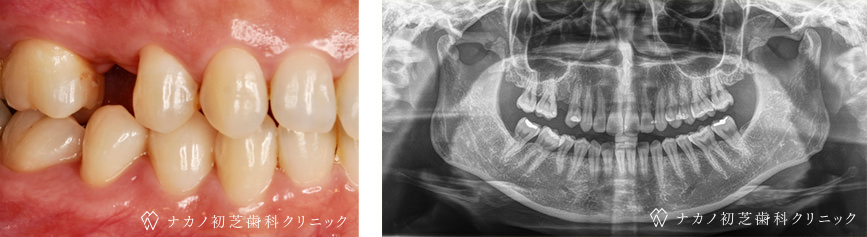

治療前

治療後

| 治療方法 | インプラント治療(骨造成と歯肉移植の併用) |

| 治療の説明 |

インプラント治療とは、歯を抜いた所にチタン製の人工歯根を埋入し、その上に歯を入れる方法です。 骨と歯肉を増やすことで、より審美的に治療が出来ました。 |

治療の副作用 (リスク) |

腫れ・疼痛・違和感を感じるなどの症状を生じることがあります。 |

| 治療費用 | 税込 440,000円/1本 |